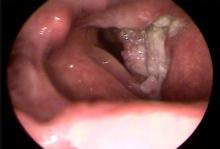

A 52-year-old man with a 40-pack-year history of smoking presented with worsening hoarseness that had begun about 6 weeks earlier. He complained of globus sensation and difficulty swallowing solid foods. He denied odynophagia, otalgia, hemoptysis, and hematemesis. There was no associated cough and he did not have any fevers, chills, or recent weight loss. The family physician (FP) performed a flexible fiberoptic laryngoscopy.

What's your diagnosis?

The FP suspected that the patient had squamous cell carcinoma (SCC) and referred him to Otolaryngology for a biopsy and workup. SCC accounts for 95% of laryngeal cancer cases. Approximately 11,000 new cases of laryngeal cancer are diagnosed in the United States each year. Peak incidence of laryngeal cancer is in the sixth and seventh decades of life with a strong male predominance.

The patient’s biopsy confirmed SCC of the larynx. Fortunately, the metastatic workup was negative and the patient underwent a laryngectomy.